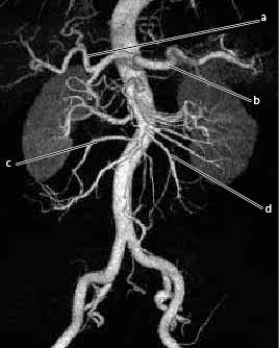

The following questions refer to the figure below of a 3D CTA of the abdominal aorta and branches.

-Which line is pointing to a jejunal branch of the abdominal aorta?